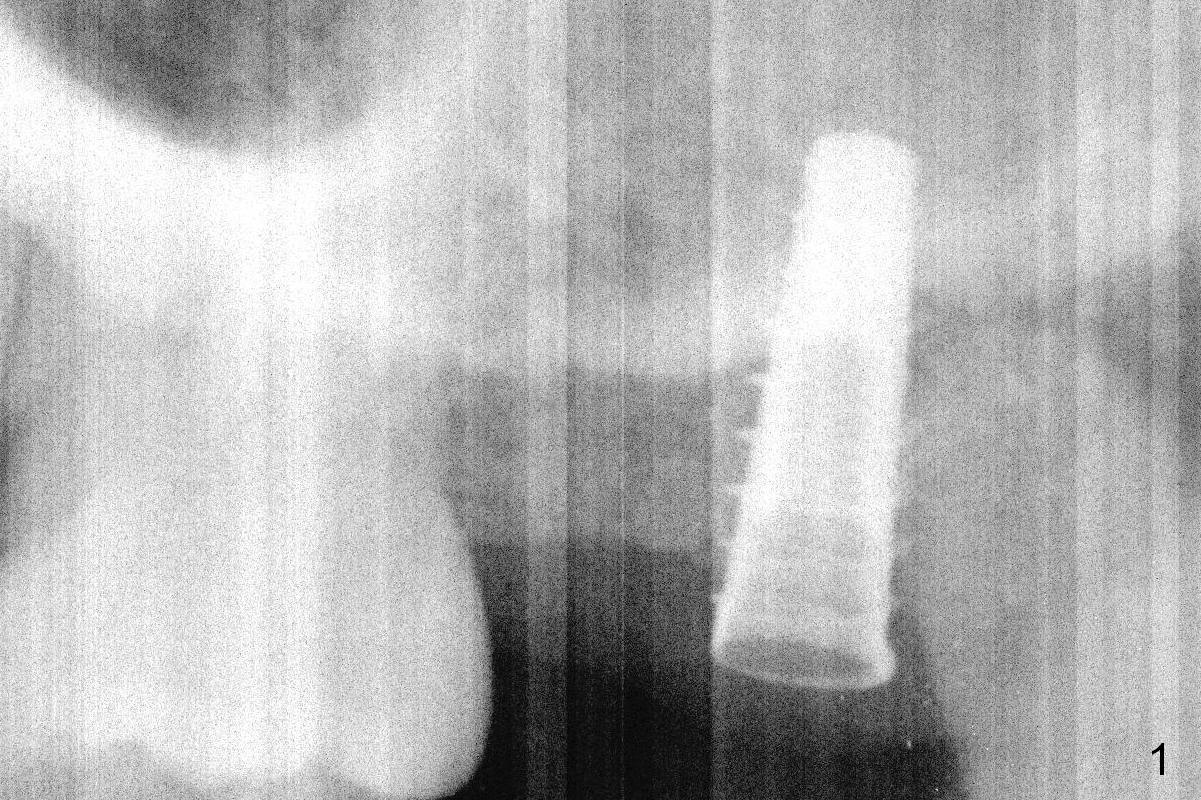

Initial osteotomy at the site of #15 for 4x11 mm dummy implant is created by #15 blade, Magic Split and Magic Expanders (ME) 3.0 and 3.8 mm (flapless, Fig.1,2, 4A (blue circle)). The implant is palatally displaced. Release incision confirms the deviation. A new osteotomy is established with 1.6 mm pilot drill in the middle of the site (Fig.4A (occlusal view) red circle). Distal to the new osteotomy is the incompletely healed socket (brown circle). As the osteotomy is enlarged by ME until 4.3 mm and placement of 4.5 and 5.0 mm dummy implant and of 5.5x9 mm definitive one (Fig.3, 4B large red circle), the osteotomy gradually deviates distopalatally. Introspectively, the new osteotomy should have been placed more buccomesially (Fig.4C red circle) so that the final osteotomy may end up normally (Fig.4D large red circle).

Because of unfavorable implant/crown ratio (Fig.3), the implant will be uncovered 6-7 months postop. An angled abutment is expected to correct the distopalatal displacement of the implant. In the meantime orthodontic treatment should start to align the malpositioned anterior teeth before extraction and implantation.